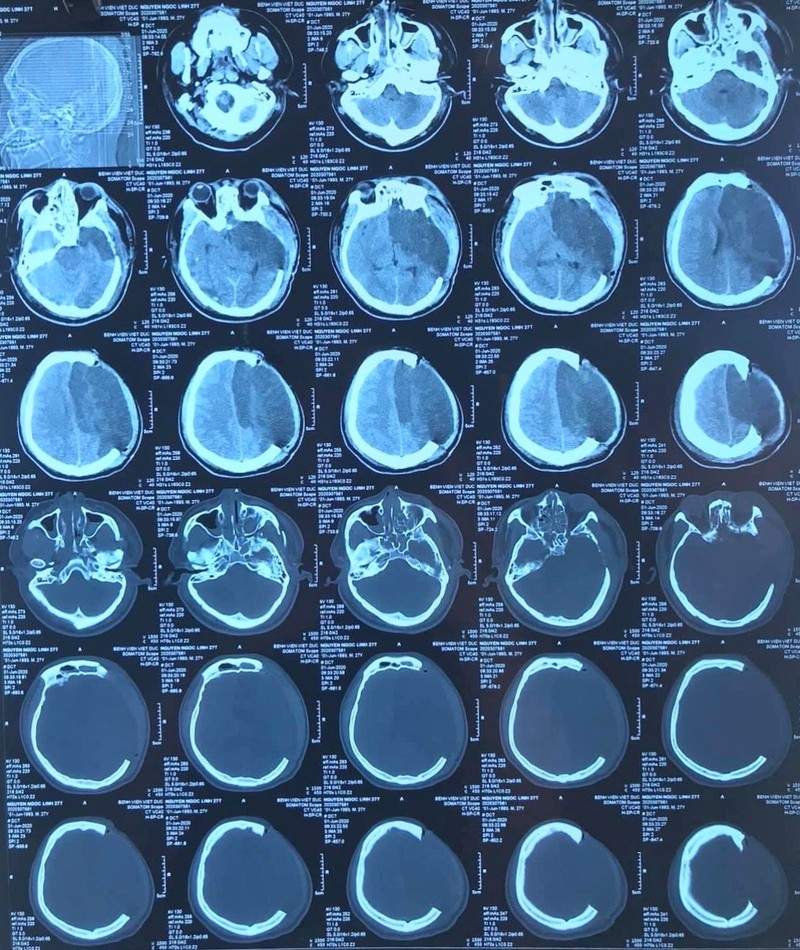

Anh N.N.L., 27 tuổi, sống ở Kiến Xương, Thái Bình không may bị ngã từ giàn giáo ở độ cao 7 m được chuyển đến Bệnh viện Hữu nghị Việt Đức vào ngày 3/6 trong tình trạng hôn mê sâu, hết sức nguy kịch.

Các bác sĩ chẩn đoán bệnh nhân bị chấn thương sọ não nặng, máu tụ DMC bán cầu T, nhồi máu bán cầu trái do hẹp động mạch cảnh trong trái, chấn thương ngực, đụng dập phổi hai bên, tràn khí trung thất. Chấn thương cột sống cổ: gãy gai sau C5C6.

Ảnh chụp hộp sọ của bệnh nhân (Ảnh: BVCC)